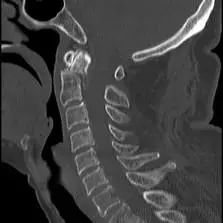

患者,男性,75岁,因外伤致颈部疼痛伴活动受限7天入院。患者入院前在当地医院确诊为:枢椎齿状突骨折Anderson-D’Alonzo分型Ⅱ型。

对于本患者来说,齿状突骨折后导致寰枢椎不稳,极易引起延髓或椎动脉损伤,严重者当场死亡。但患者同时合并严重胸腰椎后凸畸形,颈部后伸受限,不具备前路手术条件,这就给其治疗更增加了额外的困难。而由于手术部位延髓及椎动脉等血管神经密布,手术难度高、风险极大,稍有不慎,患者就会有生命危险。而患者家属在了解到手术的危险性后,曾自行到上级医院咨询专家,上级医院专家考虑围手术期死亡的风险,对于本例患者亦不愿提供手术治疗的机会。

经过全程监护和系统治疗,患者术后恢复良好,骨折解剖复位,复查X线及CT显示固定位置佳,术后3天下地行走,术后4天即出院回家休养。